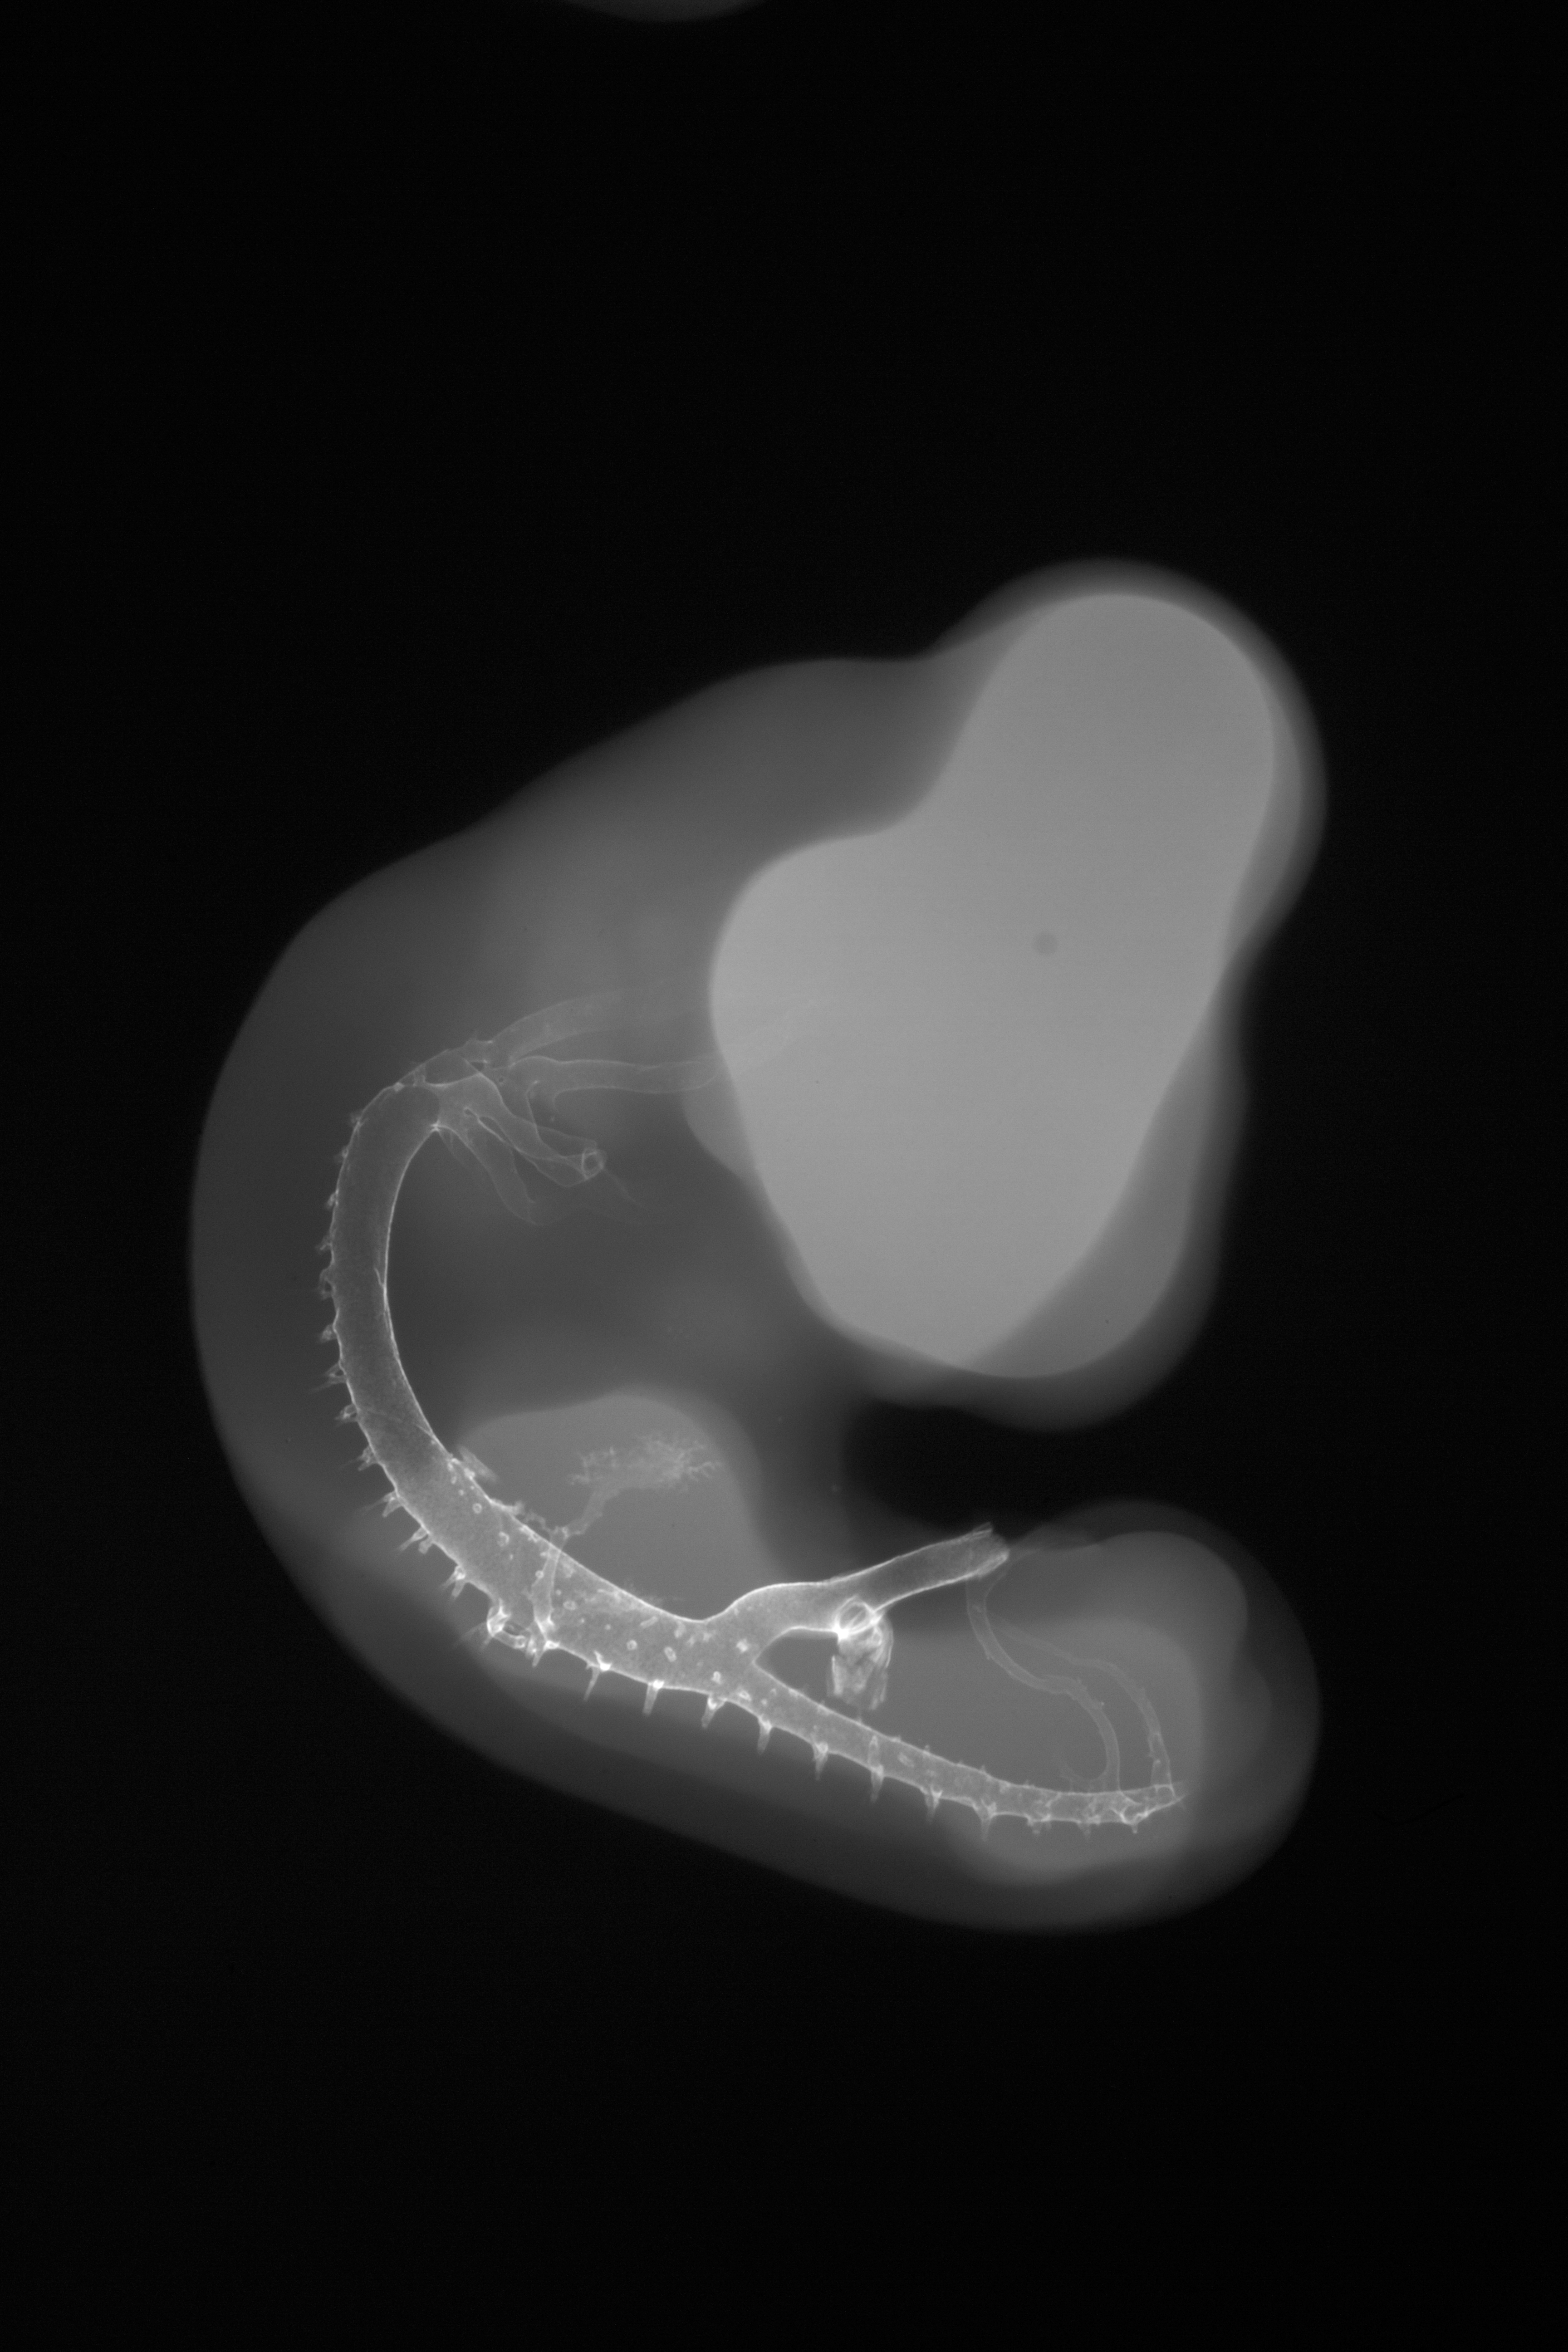

X-Ray Micrographs